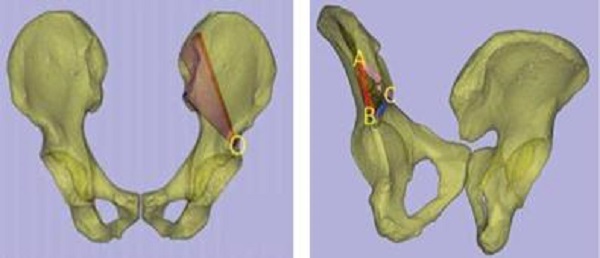

术前,创伤骨科郭永良主任医师团队应用MIMICS软件重建患者骨盆LC-II通道螺钉方向和长度,术中郭永良主任亲自主刀,使用Schanz针协助闭合复位,结合术前模拟通道螺钉方向精确制导,以最小的创伤将LC-II通道螺钉顺利置入合适位置,而且完美避开神经及血管损伤,仅通过3枚螺钉使骨盆LC-II型骨折得到有效的稳定固定。

软件重建通道螺钉位置: